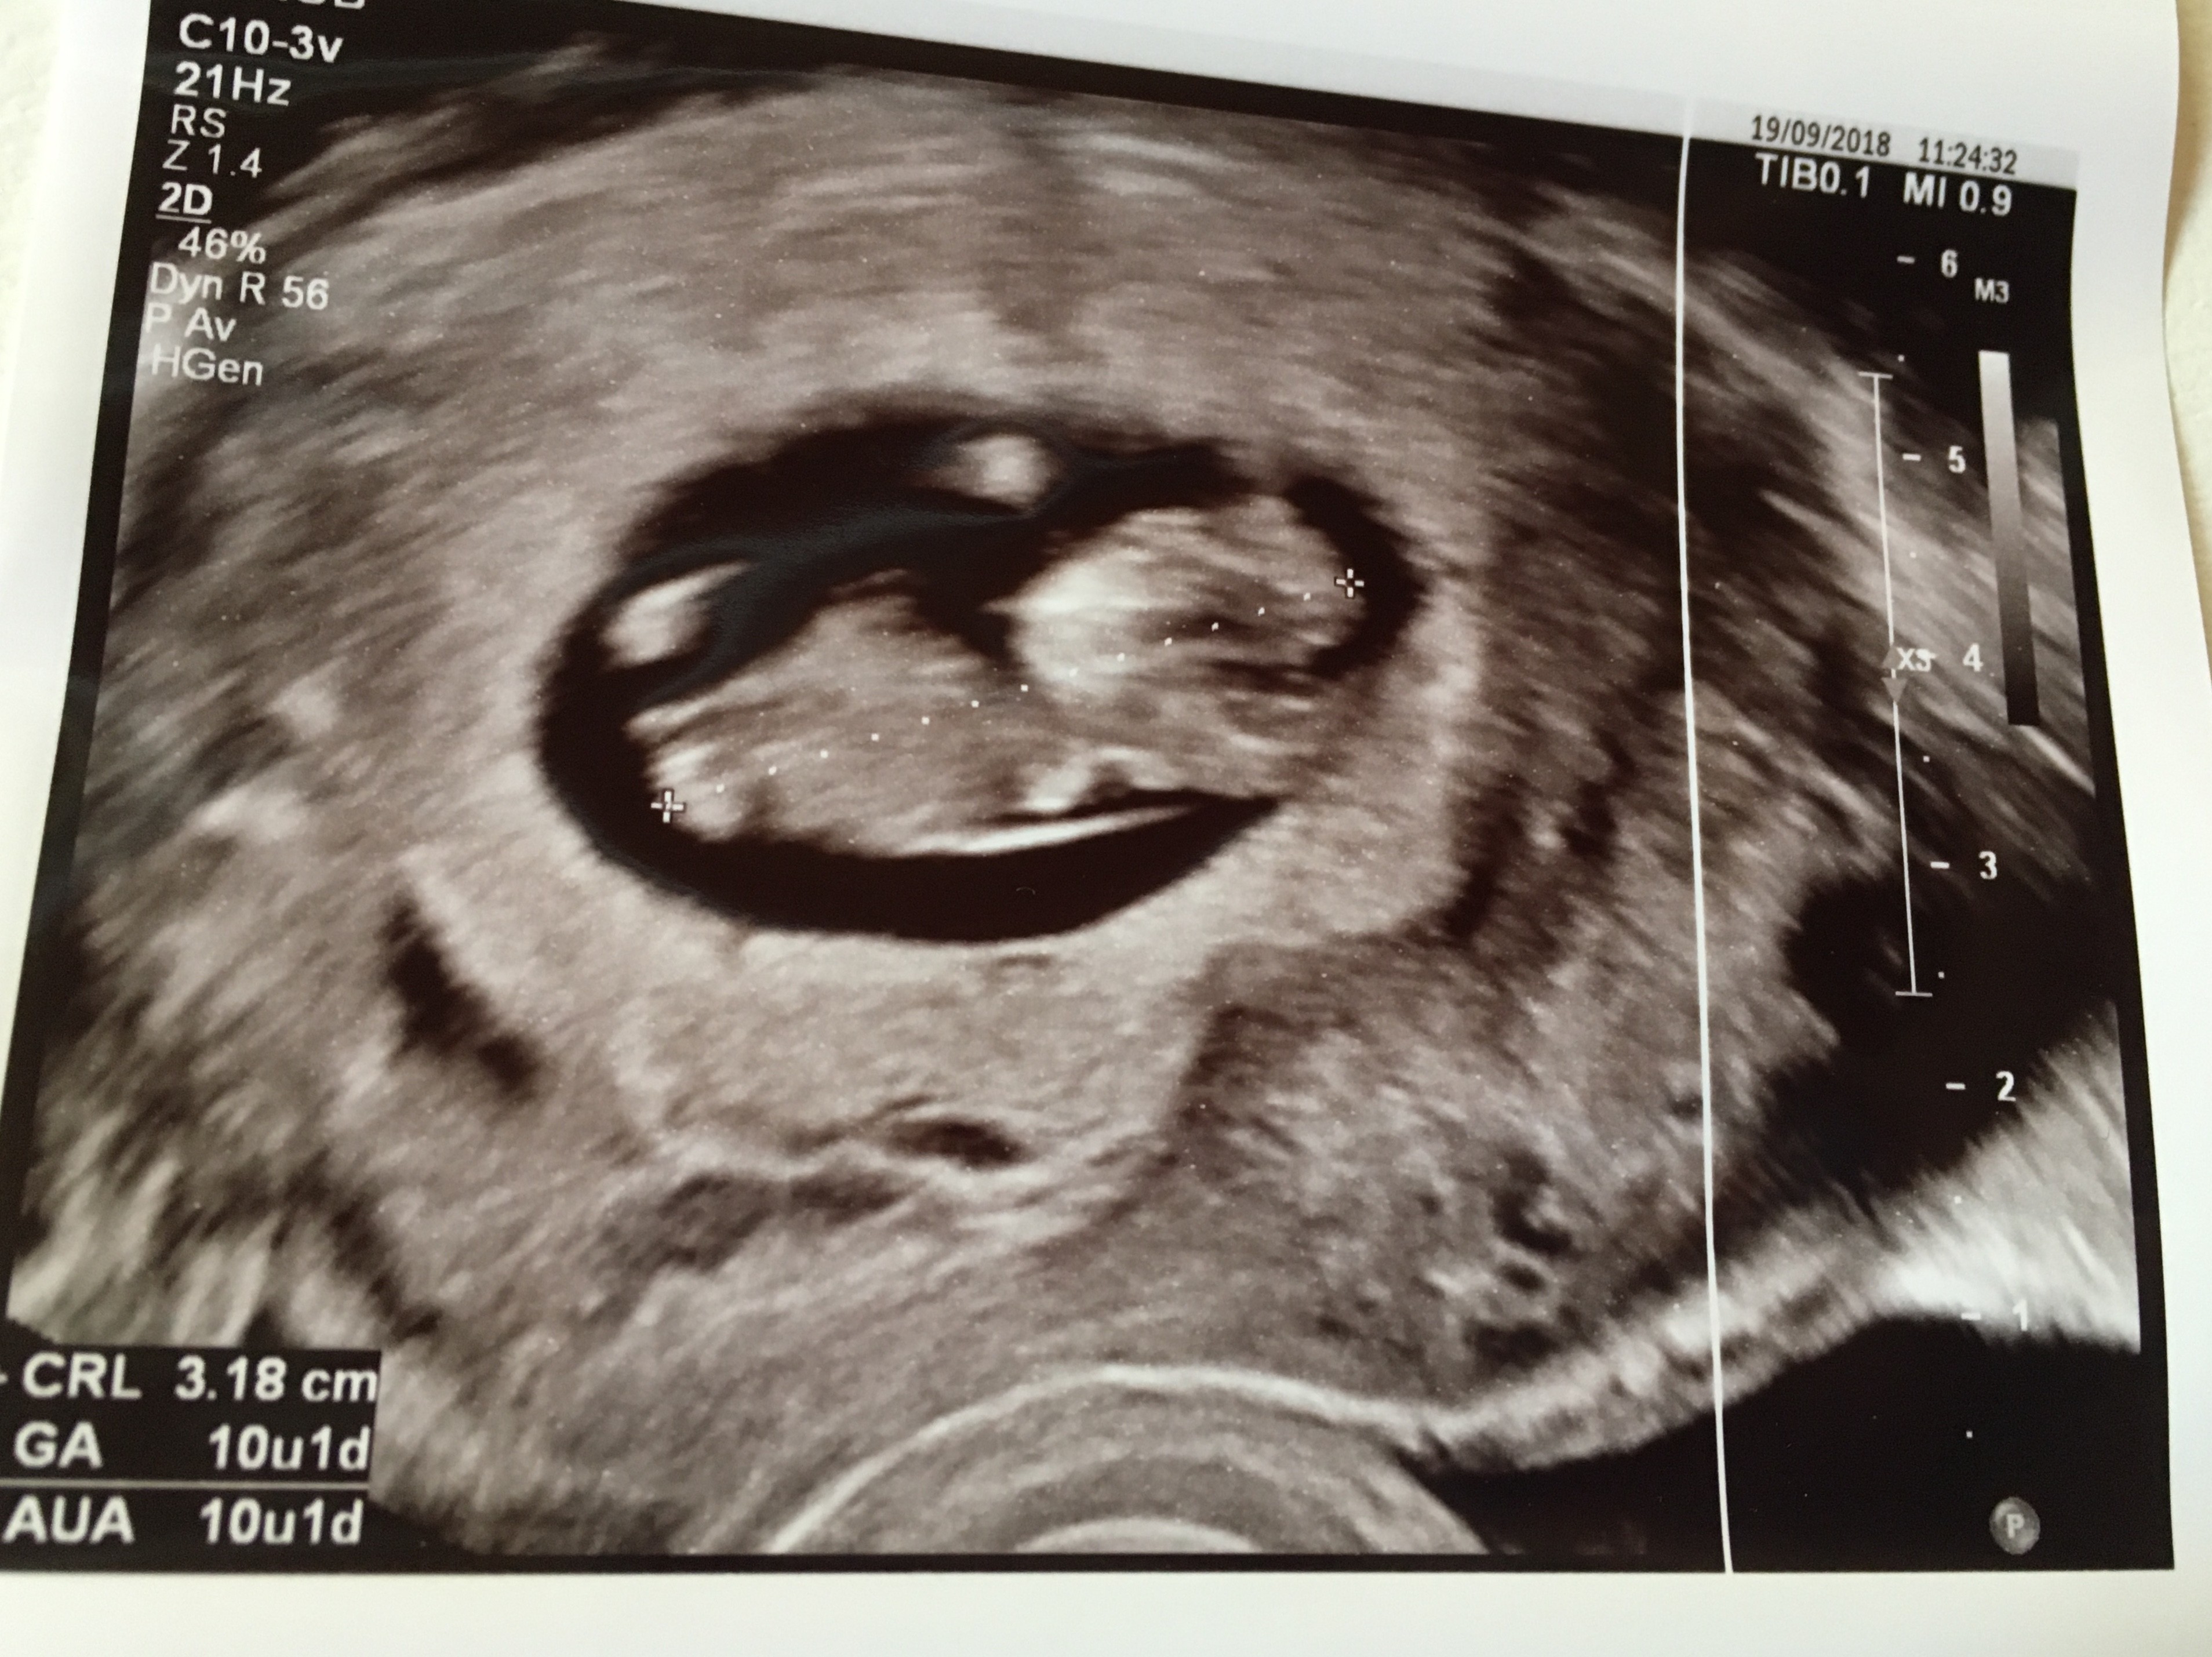

Usg miałam wykonane jeszcze dopochwowo , bo lepiej tak widać Maluszka. Jest CUDowny. Już się w nim (albo w niej) wszyscy zakochaliśmy. Maleństwo bardzo ruchliwe, widziałam rączki, nóżki, oczka..... przepiękny widok. Serduszko ślicznie bije (chociaż nie słuchałyśmy go dzisiaj). Wg OM dzisiaj jest 11+0 , wg usg 10+1, czyli już Maleństwo nadrobiło 1 dzień różnicy. Na nowo lekarka obliczyła mi termin porodu -18.04.2019 czyli Wielki Czwartek.... ale uspokoiła mnie, że w 19. tygodniu po usg oblicza się wszystko na nowo i ustala konkretną datę porodu. Dostałam już termin na to usg na 21.11.